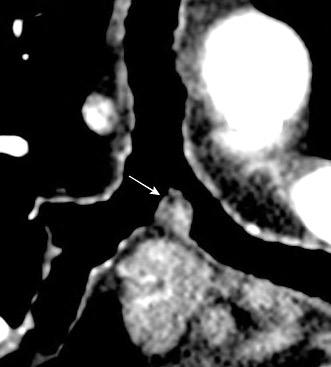

Ramana. RV et al. The “Cluster of black pearls” sign of sarcoid lymphadenopathy: a new sign on thin-section contrast-enhanced multidetector CT. Clinical Radiology 2017

2-3 cm por debajo del espacio subcarinal